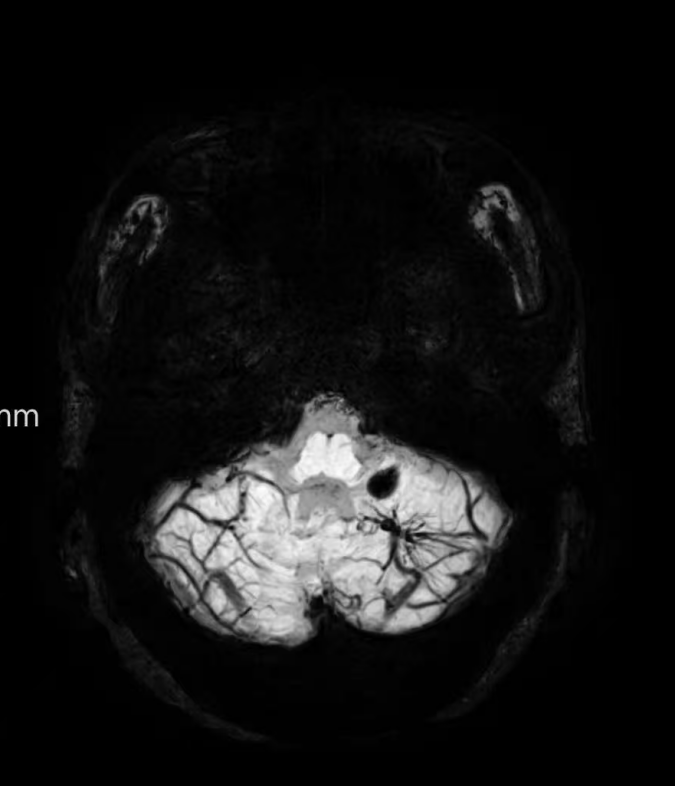

臨床中遇到一位患者,中年女性,反復出現(xiàn)頭痛,時輕時重,常規(guī)CT及磁共振檢查無明顯異常發(fā)現(xiàn),最后建議加做一個磁共振磁敏感加權成像(SWI),結果發(fā)現(xiàn)是左側小腦發(fā)育性靜脈畸形(DVA),SWI清晰顯示畸形的靜脈及周圍含鐵血黃素沉積;如下圖。這正是她頭痛的原因。

①診斷靜脈畸形:SWI能高精度地顯示發(fā)育性靜脈畸形——一種常見的腦血管畸形。在SWI上,發(fā)育性靜脈畸形會呈現(xiàn)典型的“海蛇頭”或“水母頭”征,即一堆細小的髓靜脈匯入一支粗大的引流靜脈。